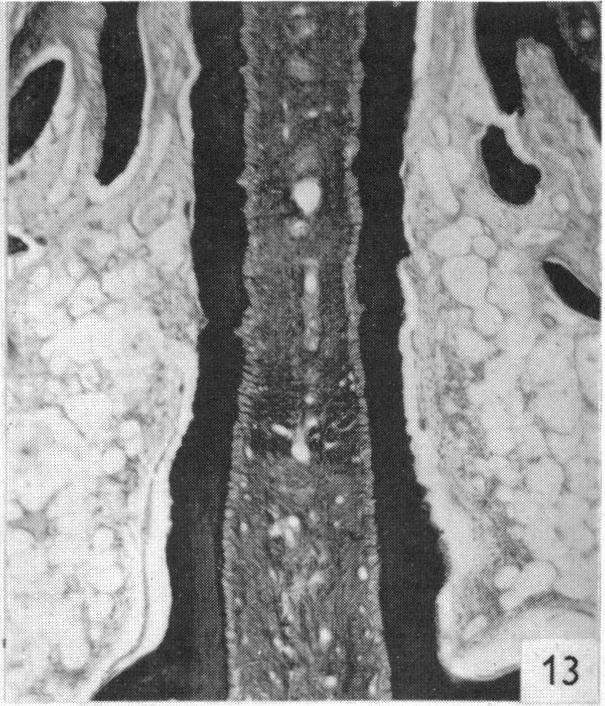

The structure and development of cranial and facial sutures.

PRITCHARD J J, SCOTT J H, GIRGIS F G

J Anat. 1956 Jan;90(1):73-86.